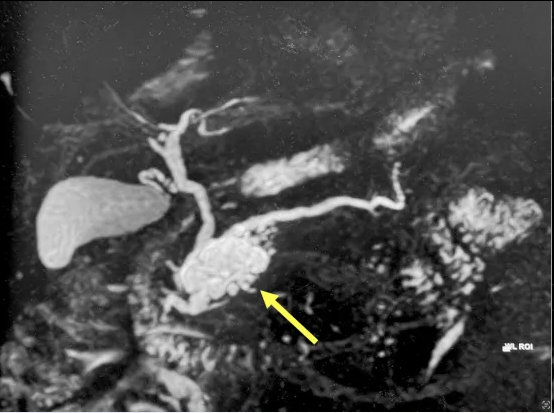

▲MRCP图像可同时观察肝内外胆管、胆囊和胰管,本例患者可能为胰腺导管内乳头状黏液性肿瘤(IPMN)